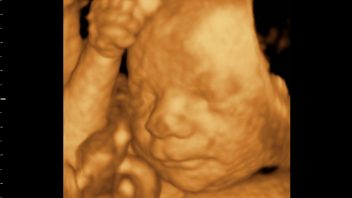

Lucinka právě prožívá 29. týden těhotenství. Jak roste její miminko v bříšku a co se děje s ní?